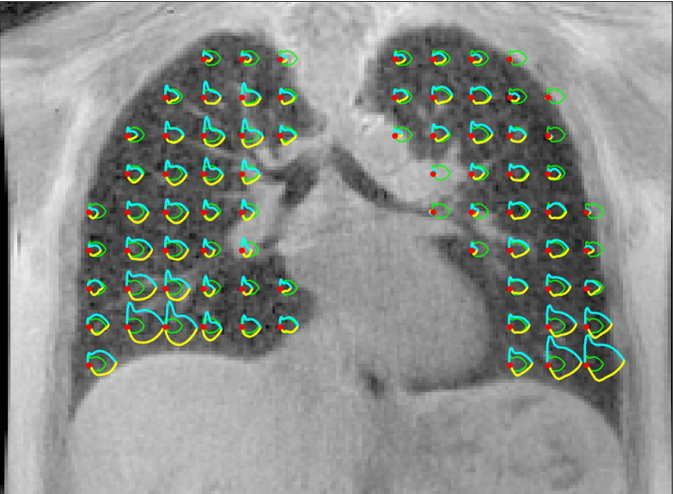

The 3D MR spirometry workflow developed by V|LF-Spiro3D has introduced several innovative features:

(1) New biomechanical biomarkers along normal strains.

(2) An original phase-portrait retrospective gating method for 3D lung dynamic MRI data.

(3) An automatic deep segmentation scheme.

(4) A semi-automatic vessel-based lobar segmentation of the lung.

These advancements have been published, though the core processing algorithm remains undisclosed. These developments establish 3D MR spirometry as a robust tool for assessing lung function and have potential applications in other lung MRI techniques. However, these are preliminary steps, and further work is needed: